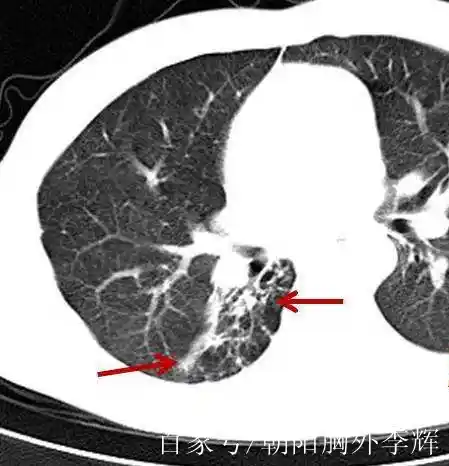

纤维条索影是医学影像学上的一个术语,通常在胸部X光或CT扫描中出现,表现为一条或多条细线样的影像。这种影像的病理基础是纤维组织的存在,它们可能来源于纤维母细胞、血管内皮细胞、结缔组织等的增生。纤维条索影的形成通常与以下几种情况有关:

- 慢性感染:如肺结核或肺炎后,经过治疗,病灶吸收后可能遗留下瘢痕,形成纤维条索影。

- 炎症:长期慢性刺激下,肺部组织可能形成陈旧性病灶,常见于肺结核患者或肺炎、支气管炎患者。

- 既往病变:纤维条索影可能是既往病变经过治疗或自身防御反应后,大部分吸收好转,仅遗留有纤维化部分的表现。

- 其他原因:包括支气管扩张、慢性阻塞性肺疾病、肺纤维化以及长期吸烟的人群也可能表现出纤维条索影。